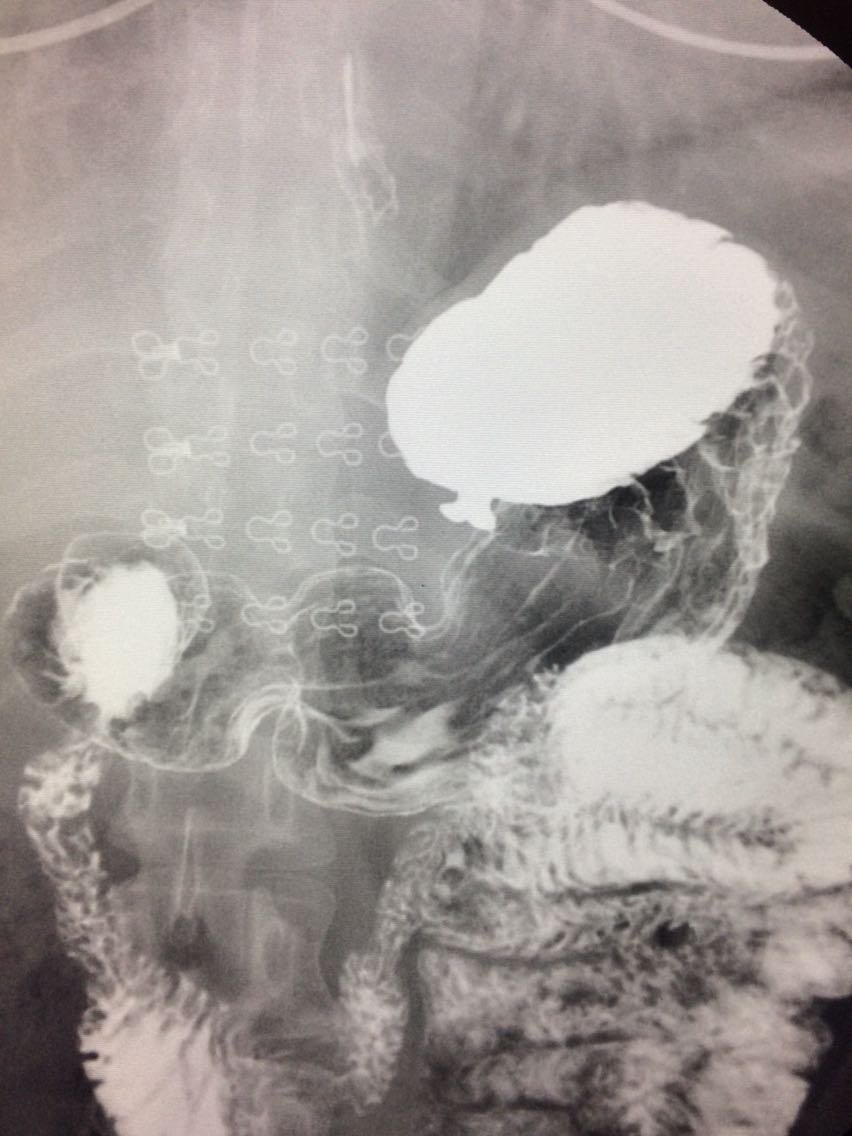

胃底憩室一例

女.47岁 体检来诊。 平素体健,无明显症状。 做上消化道造影如图。

诊断,胃底憩室。 治疗,患者无明显症状,未予治疗。